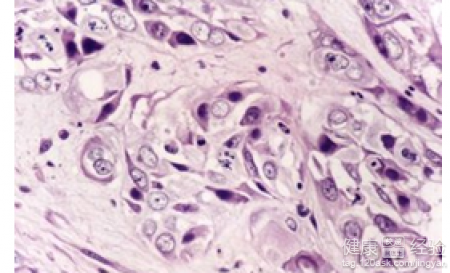

高熱驚厥會有突然之間發作,而且比較恐怖的症狀出現的。有的孩子甚至是身體僵直,沒有意識。叫他也不會應答的程度的。孩子往往會有雙眼球凝視的症狀和斜視的症狀。有得孩子在高熱驚厥發作的時候,會有眼睛發直的症狀和眼睛上翻的症狀。有高熱驚厥的孩子往往伴意識喪失。高熱驚厥的病人需要科學的護理,減少發作的。高熱驚厥史能否打乙腦和流腦?